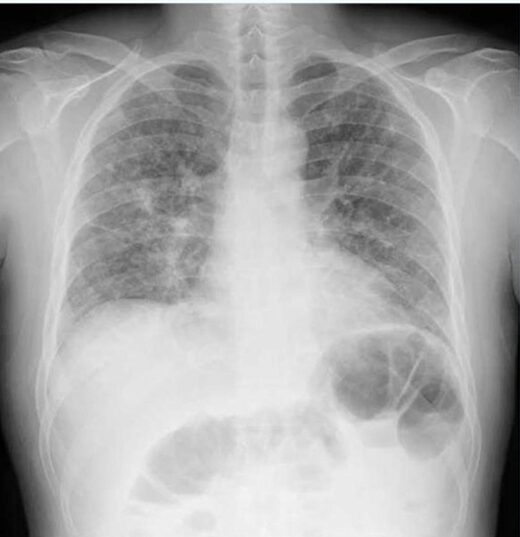

間質性肺炎の胸部レントゲン(X-p)所見

間質性肺炎はウイルス感染(COVID19肺炎でも起こります)や膠原病を含めた自己免疫性疾患、薬剤性や特発性にも起こる肺炎です。

レントゲンの特徴として下記のような所見があります。

すりガラス影(すりガラス様陰影):

肺胞内に分泌物があることで、全体がうっすらと白っぽく見える状態です。初期の間質性肺炎でよく見られる所見です。

粒状影:

肺の組織に細かい点状の白い影が多数見られる状態です。

網状影(網の目状の影):

肺に網の目のような白い線が見られる所見で、肺の間質に炎症が起きていることを示します。

蜂巣肺(ほうそうはい):

間質性肺炎が進行し、肺が線維化して硬くなると現れる、蜂の巣状の開口した陰影です。

びまん性病変:

これらの影が、肺全体に広がって見えることがあります。

本症例では肺が小さく、横隔膜が挙上し両側肺野に、もやもやした濃度上昇(両側のすりガラス陰影)があることが確認できます。

このような場合に間質性肺炎を疑います。